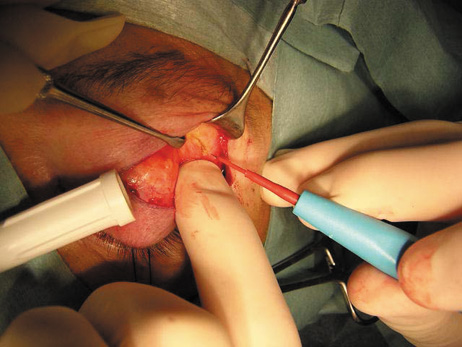

wall still can be carried out. | Fig. 9. A,B. Coronal and axial CT images of a large intraconal neoplasm. C. Because it was felt to represent a well-encapsulated cavernous hemangioma, this

lesion was a candidate for removal via an eyelid crease orbitotomy

without bone removal. The eyelid crease incision marked. D. Incision made with scalpel. E. Orbicularis muscle is tented up and incised to expose the underlying septum. F. Dissection of a skin-muscle flap deep to orbicularis exposes the orbital

septum and superior orbital bony rim. G. Cutting cautery is used to incise periosteum along the superior and lateral

rims; finger palpation of the bone helps to direct this incision. H. Periorbita is elevated along the mesial surface of the lateral orbital

rim in order to expose the deep orbital tissues. I. The cavernous hemangioma is visualized in the wound. Retraction is provided

by one or more malleable retractors. J. Cryoprobe is affixed to the hemangioma to facilitate manipulation of the

lesion. K. Large cavernous hemangioma after removal through the eyelid crease incision

which was accomplished without bone removal. L. Periorbita is reattached over the lateral rim. M. The eyelid crease incision is closed with a running suture. |